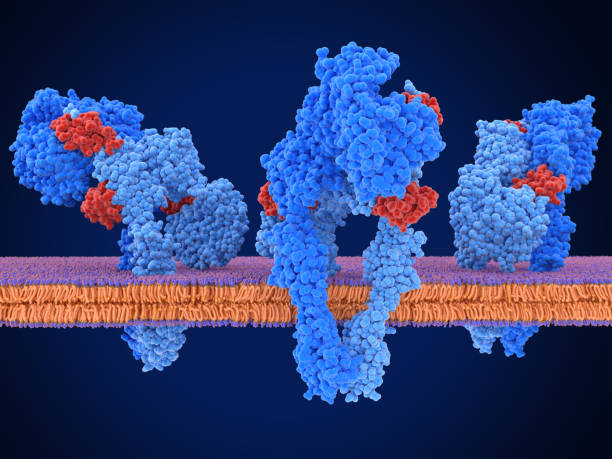

Las hormonas son producidas por las glándulas endocrinas y liberadas al torrente sanguíneo. A partir de ahí, se transportan a través del cuerpo hasta llegar a las células diana, donde se unen a receptores específicos en la membrana celular o en el interior de la célula. Cuando una hormona se une a su receptor, se desencadena una cascada de eventos bioquímicos en el interior de la célula, que pueden afectar el crecimiento, la diferenciación, el metabolismo y otras funciones celulares.

Las hormonas pueden ser de varios tipos, incluyendo esteroides, proteínas, aminas y péptidos. Cada tipo de hormona interactúa con receptores específicos en la célula diana. Por ejemplo, las hormonas esteroides pueden penetrar en la célula y unirse a receptores intracelulares, mientras que las hormonas proteicas se unen a receptores en la membrana celular.